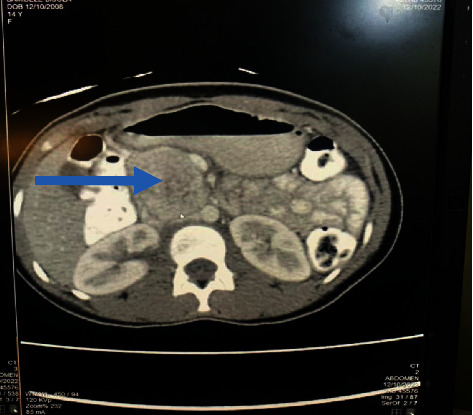

Introduction: A paraganglioma (PGL) is a tumour derived from extra-adrenal chromaffin cells of the sympathetic paravertebral ganglia of the thorax, abdomen, and pelvis. Cardiovascular manifestations predominate but neurological symptoms like seizures can occur requiring a high index of suspicion for prompt diagnosis and treatment. Case Description. A 14-year-old girl was referred to the paediatric neurology unit for recurrent headaches of one-year duration, vomiting of 2 months duration, and an episode of generalized tonic-clonic seizures, 2 weeks prior to presentation. There was an associated history of impaired vision, palpitations, diaphoresis, and easy fatigability. Her blood pressure ranged from 150/101 to 160/120 mmHg. The brain CT scan was normal. ECG showed left ventricular hypertrophy. Abdominal USS revealed a right para-aortic mass necessitating 24-hour urine normetanephrine which was markedly elevated-1695.34 mcg/24 h (100-500). An abdominal CT scan confirmed a paraganglioma in the right para-aortic region. A multidisciplinary team consisting of paediatric endocrinologists, radiologists, anaesthetists, paediatric and cardiothoracic surgeons, and the intensive care unit (ICU) team was involved in the peri and postoperative management of the child. Intraoperative challenges were hypertension and hypotension (following tumour excision). She was nursed in the ICU for 48 hours. Histology results confirmed paraganglioma. Postoperative urine normetanephrines done a month after surgery had reverted to normal. Her blood pressure has remained normal 6 months after surgery, and no other symptoms have recurred.

Abstract Image